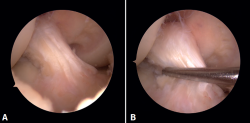

reaca.32385.fs2409018-figura2.png

Figura 2. Imagen de resonancia magnética del quiste sinovial localizado en el ligamento cruzado anterior en cortes sagitales. A: secuencia DP FS en corte sagital de la rodilla; B: secuencia DP T1 en corte sagital de la rodilla.

En las pruebas complementarias no presentaba alteraciones óseas en las radiografías en carga anteroposterior y lateral de rodilla. El estudio mediante RM evidenció un ganglión sinovial intercondilar de 25 mm (Figura 2).